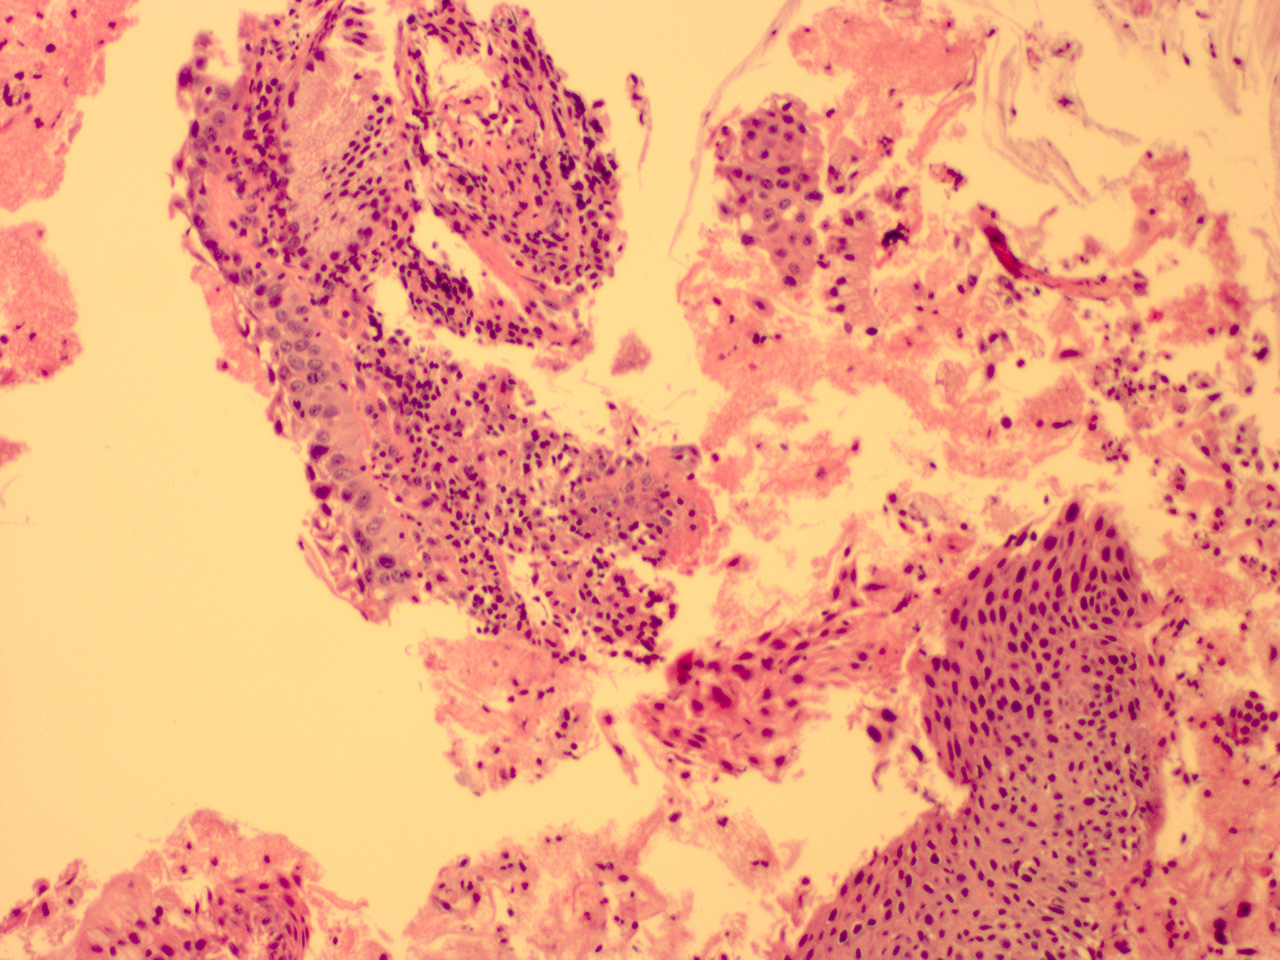

Case 7

Soft ECC CIN 2

40x - High Power |